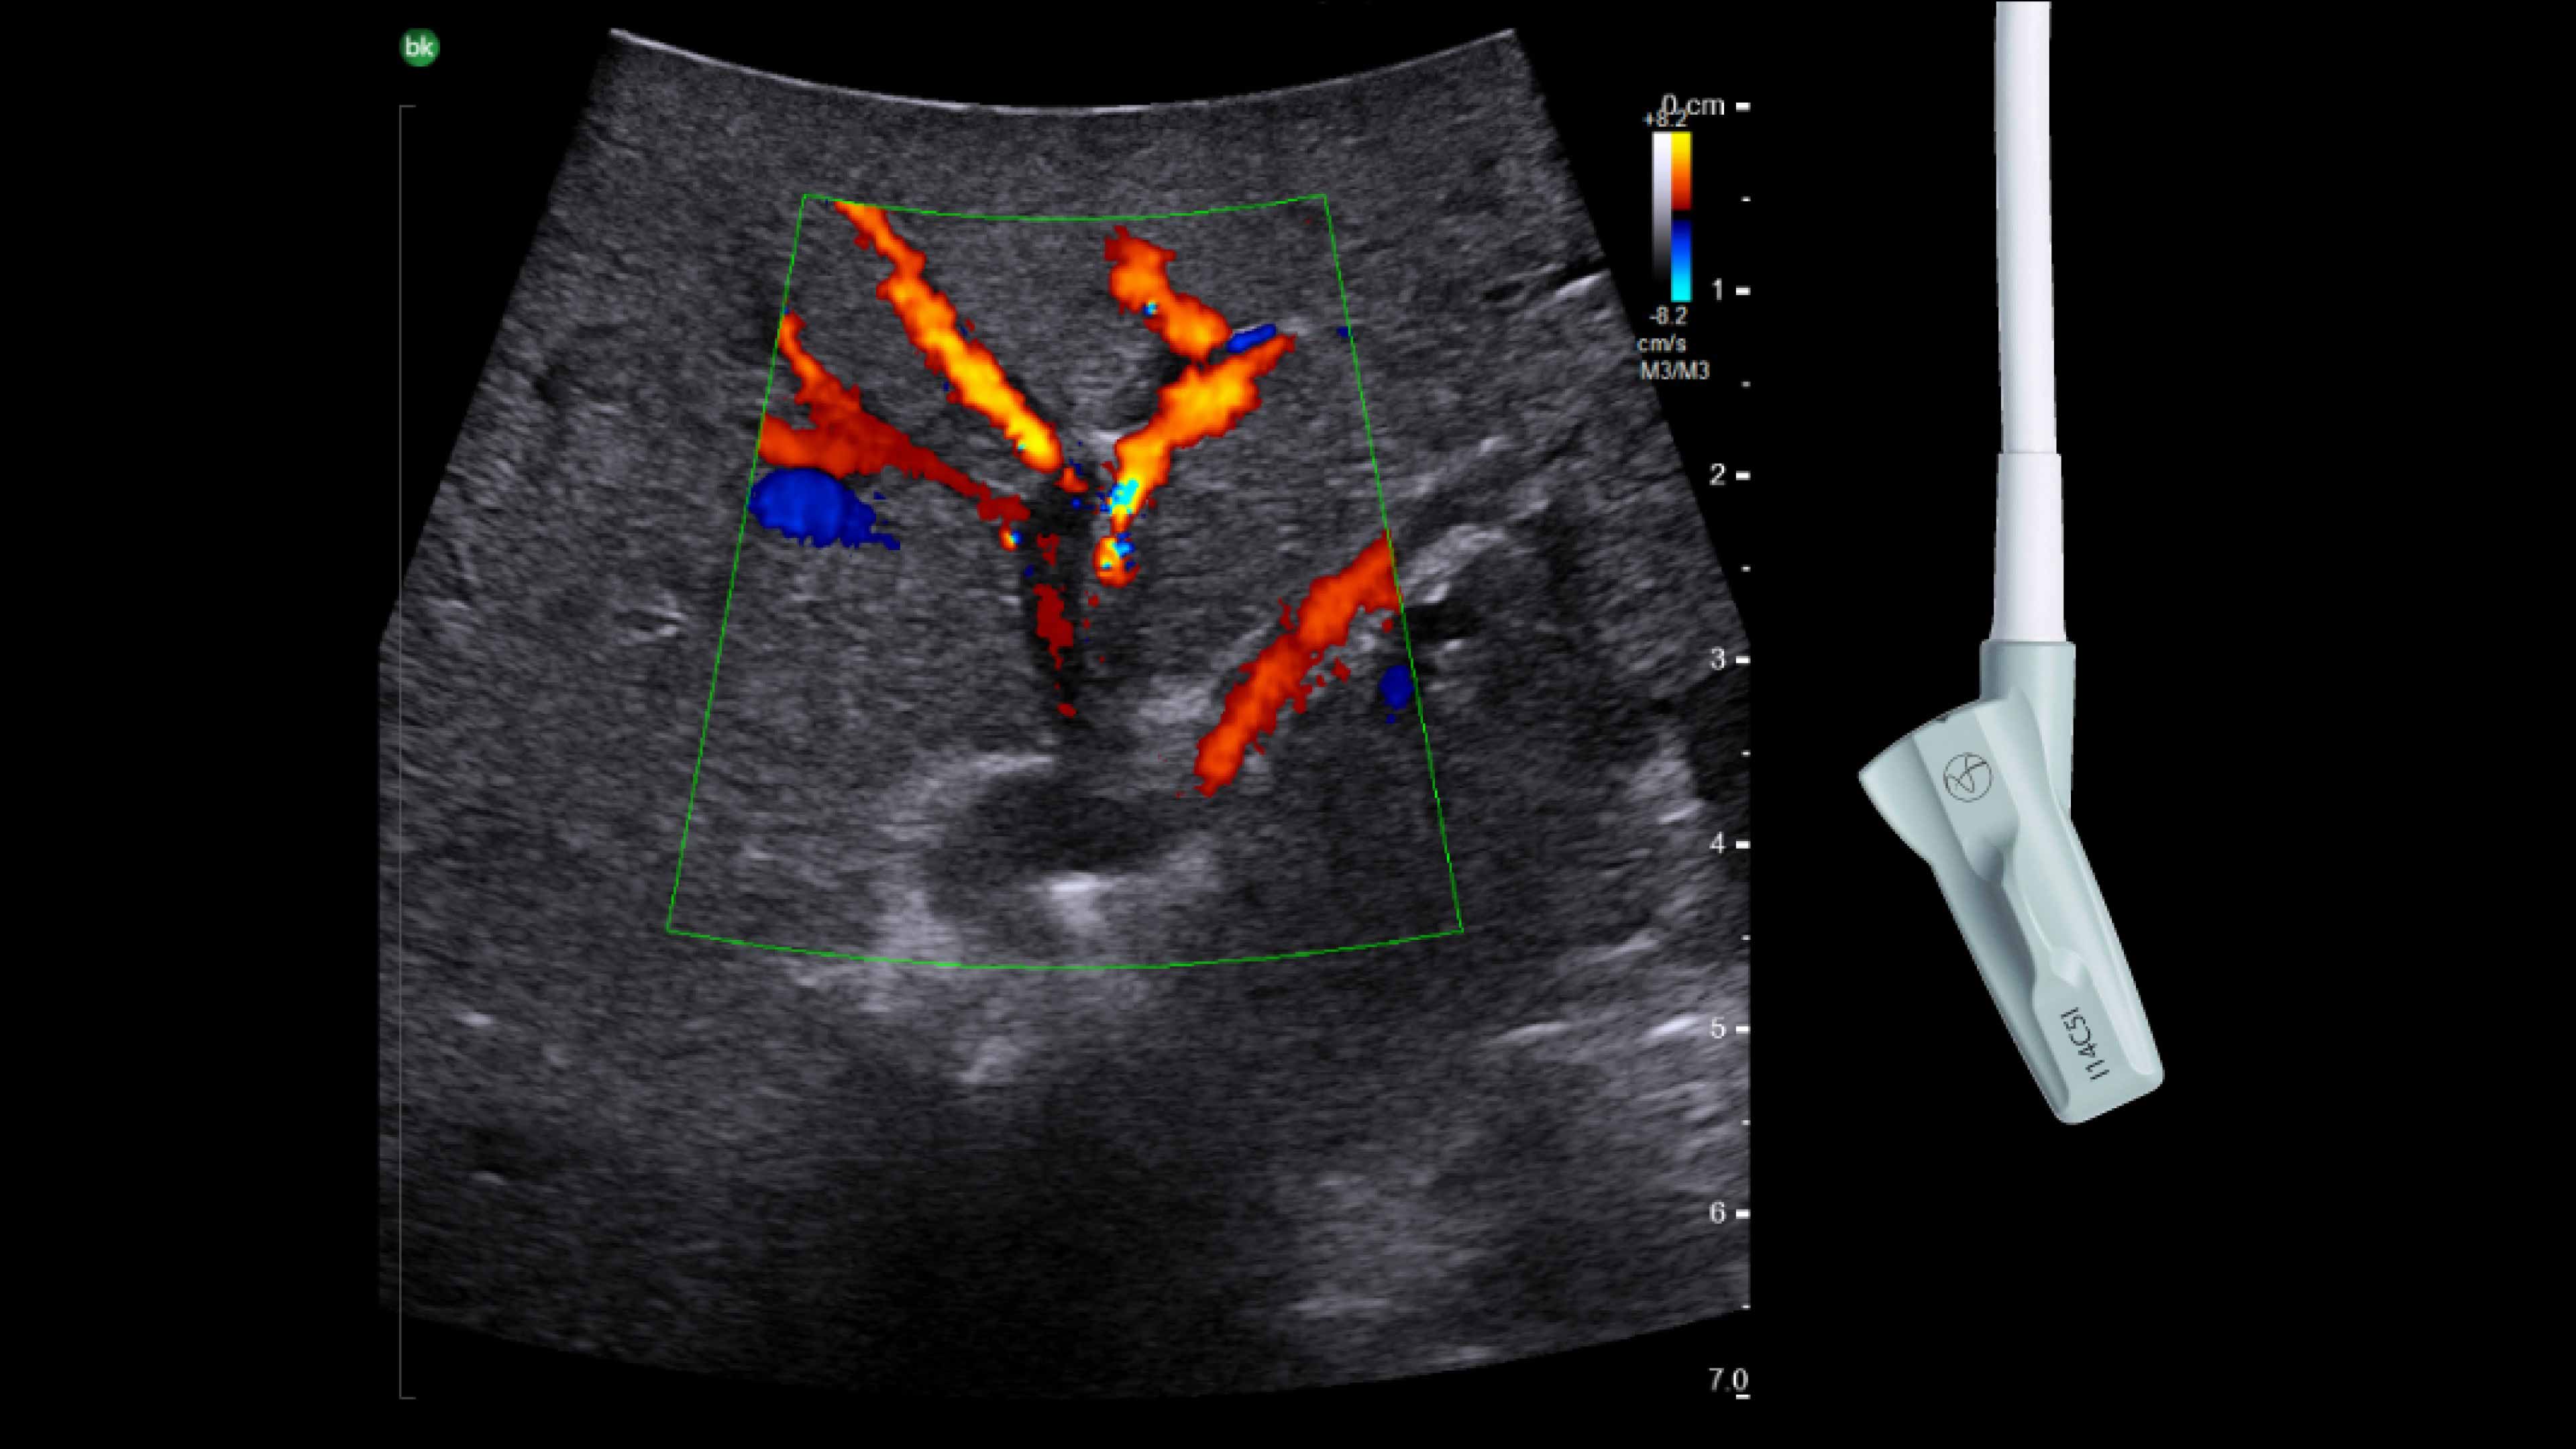

Imaging to guide cholecystectomies

Discover the clinical benefits of active imaging with intraoperative ultrasound for laparoscopic cholecystectomy procedures. Using bkActiv and the Advanced Laparoscopic Transducer, surgeons can visualize anatomy and monitor progress as many times as needed during the procedure.

The value of iUS in cholecystectomies

iUS is beneficial for cholecystectomies due to its safety, quick and repeatable imaging capabilities and ability to detect choledocholithiasis and enable visualization of biliary tract anatomy.

• iUS has minimal safety risks as it is non-irradiating and does not required cannulation. ¹⁻³

• iUS can be used dynamically throughout dissection adding minimal time to a cholecystectomy procedure. iUS can also repeated, helping to assess common bile duct integrity at the end of the procedure.¹⁻⁵

• iUS helps differentiate between sludge, stone, polyps, cysts, and tumors when determining if there is a presence of gallstones in the common bile duct.⁵,⁶

• iUS uses color flow doppler to help differentiate between vessels and ducts and is overall effective at imaging difficult cases such as inflammation or fibrosis .¹,⁴⁻⁶